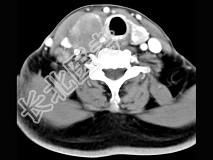

- 多项选择题女性,54岁, 右侧颈部肿大近1年,近来病人有声嘶、吞咽困难, CT扫描如图,请选择正确的描述和答案 ( )

A、右侧甲状腺肿大,密度减低

B、增强扫描示甲状腺呈不规则强化团块影,其内有低密度区,病灶境界不清

C、右侧颈内静脉增粗,其内可见不规则充盈缺损区

D、考虑甲状腺癌

E、右侧颈内静脉瘤栓形成